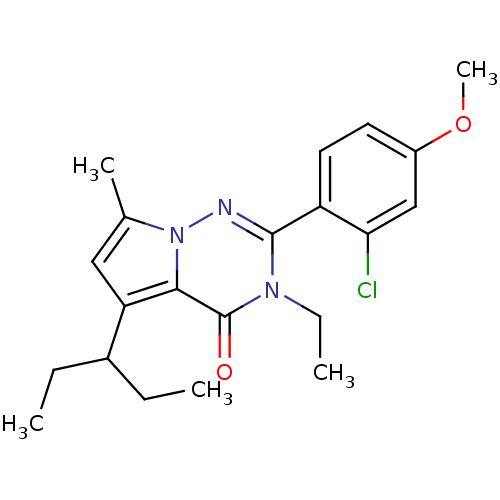

TargetCorticotropin-releasing factor receptor 1(Homo sapiens (Human))

Dupont Pharmaceuticals

Curated by ChEMBL

Dupont Pharmaceuticals

Curated by ChEMBL

Affinity DataEC50: 0.300nMAssay Description:Antagonist activity at human CRF1 receptor expressed in CHO-K1 cells assessed as CRF-stimulated cAMP accumulation by enzyme immunoassayMore data for this Ligand-Target Pair

Affinity DataEC50: 0.420nMAssay Description:Antagonist activity at CRF-R1 in mouse AtT-20 cells assessed as inhibition of human CRF induced cAMP accumulation after 30 mins by radioimmunoassayMore data for this Ligand-Target Pair

Affinity DataEC50: 0.440nMAssay Description:Antagonist activity at CRF-R1 in mouse AtT-20 cells assessed as inhibition of human CRF induced cAMP accumulation after 30 mins by radioimmunoassayMore data for this Ligand-Target Pair

Affinity DataEC50: 0.450nMAssay Description:Antagonist activity at CRF-R1 in mouse AtT-20 cells assessed as inhibition of human CRF induced cAMP accumulation after 30 mins by radioimmunoassayMore data for this Ligand-Target Pair